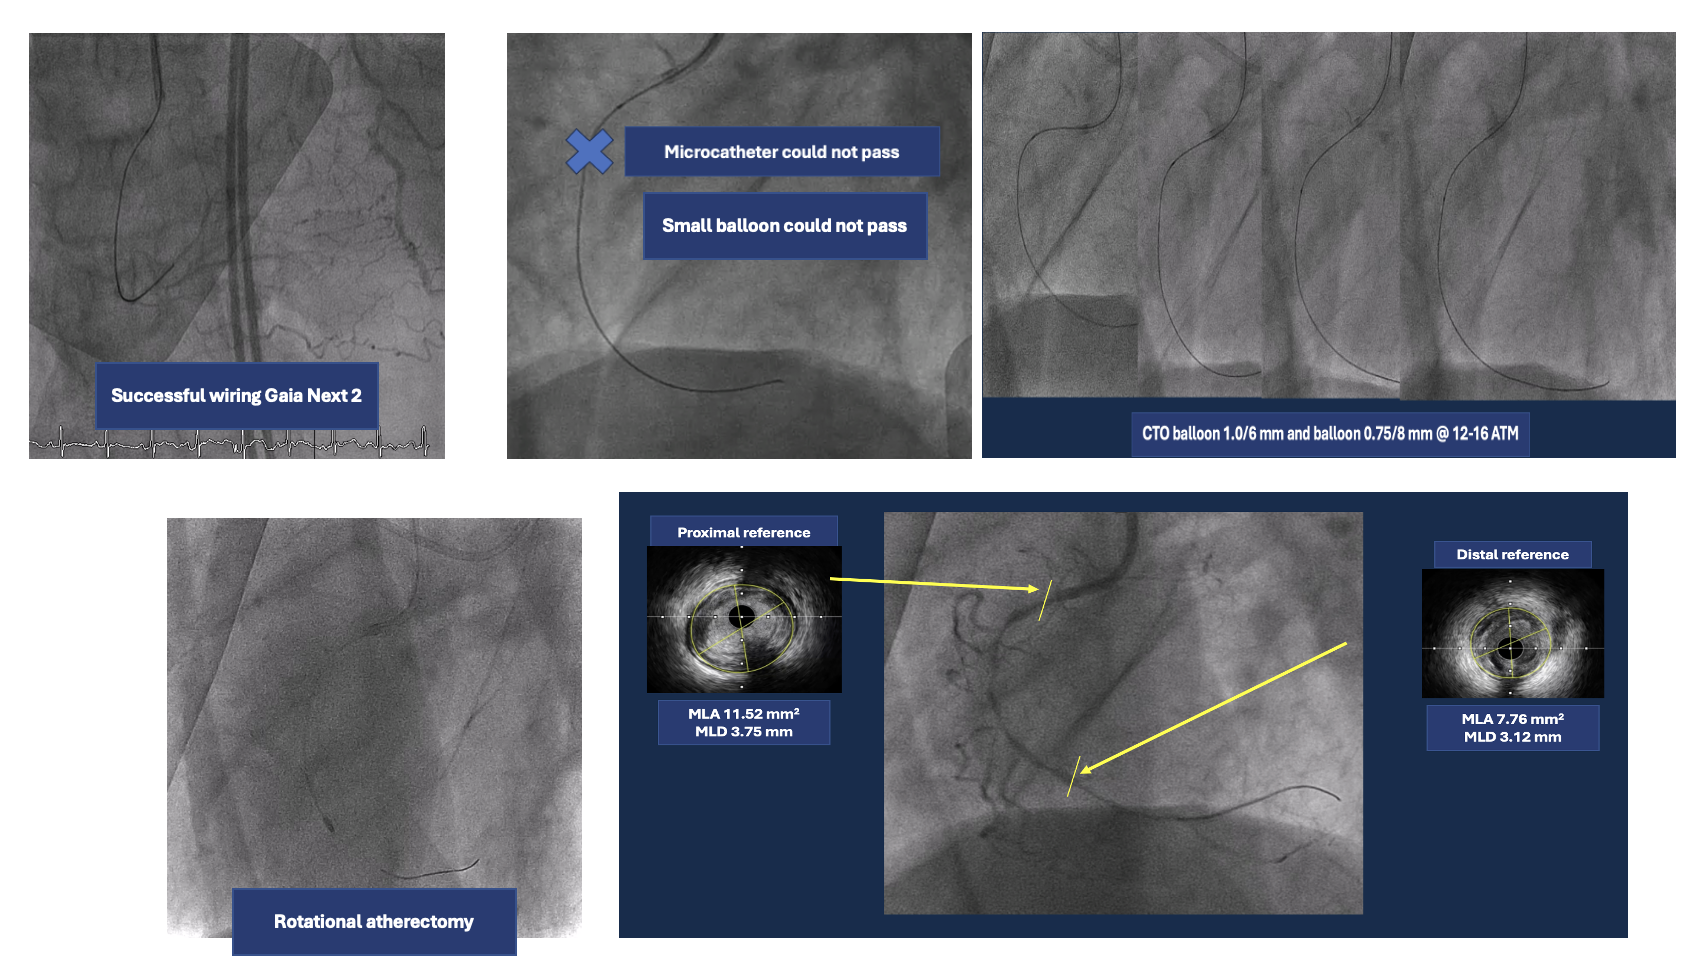

A 6 Fr JR 4.0 guiding catheter was engaged via femoral approach and JL 4 catheter was used for dual injection. We planned to perform PCI at proximal RCA CTO with antegrade wire escalation technique first. We successful wired to PL branch of RCA using microcatheter with Gaia Next 2 guidewire (Failed using Fielder XT). The microcatheter could not cross lesion. Try using CTO balloon 0.75/8 mm and 1.0/6 mm to pre-dilatation but still uncrossable. So we put the microcatheter farthest and successful bare wiring the RotaWire Floppy to PL. Rotational atherectomy was done with Burr 1.25 mm at 172,000 - 146,000 rpm total 4 runs. IVUS was pulled back from PL-RCA showed intra-plaque wiring, calcified nodules with cracked calcific plaques and reverberation. We prepared the lesion proximal to mid RCA lesion with non-compliant 2.5/15 mm balloon at 20 atm and scoring 3.0/13 mm balloon at 18-20 atm. A 3.0/38 mm stent could not be delivered the lesion. We used the guide extension catheter with balloon-assisted tracking techinque for delivery. The stent was successfully deployed to mid RCA. The 3.5/28 mm stent was deployed to proximal to mid RCA and 3.5/18 mm stent was deployed at ostial RCA. Post-dilatation with non-compliant 3.0/15 and 3.5/18 mm at 16 atm. Final angiogram showed good coronary blood flow and IVUS demonstrated well stent expansion, no malapposition and no stent edge dissection.